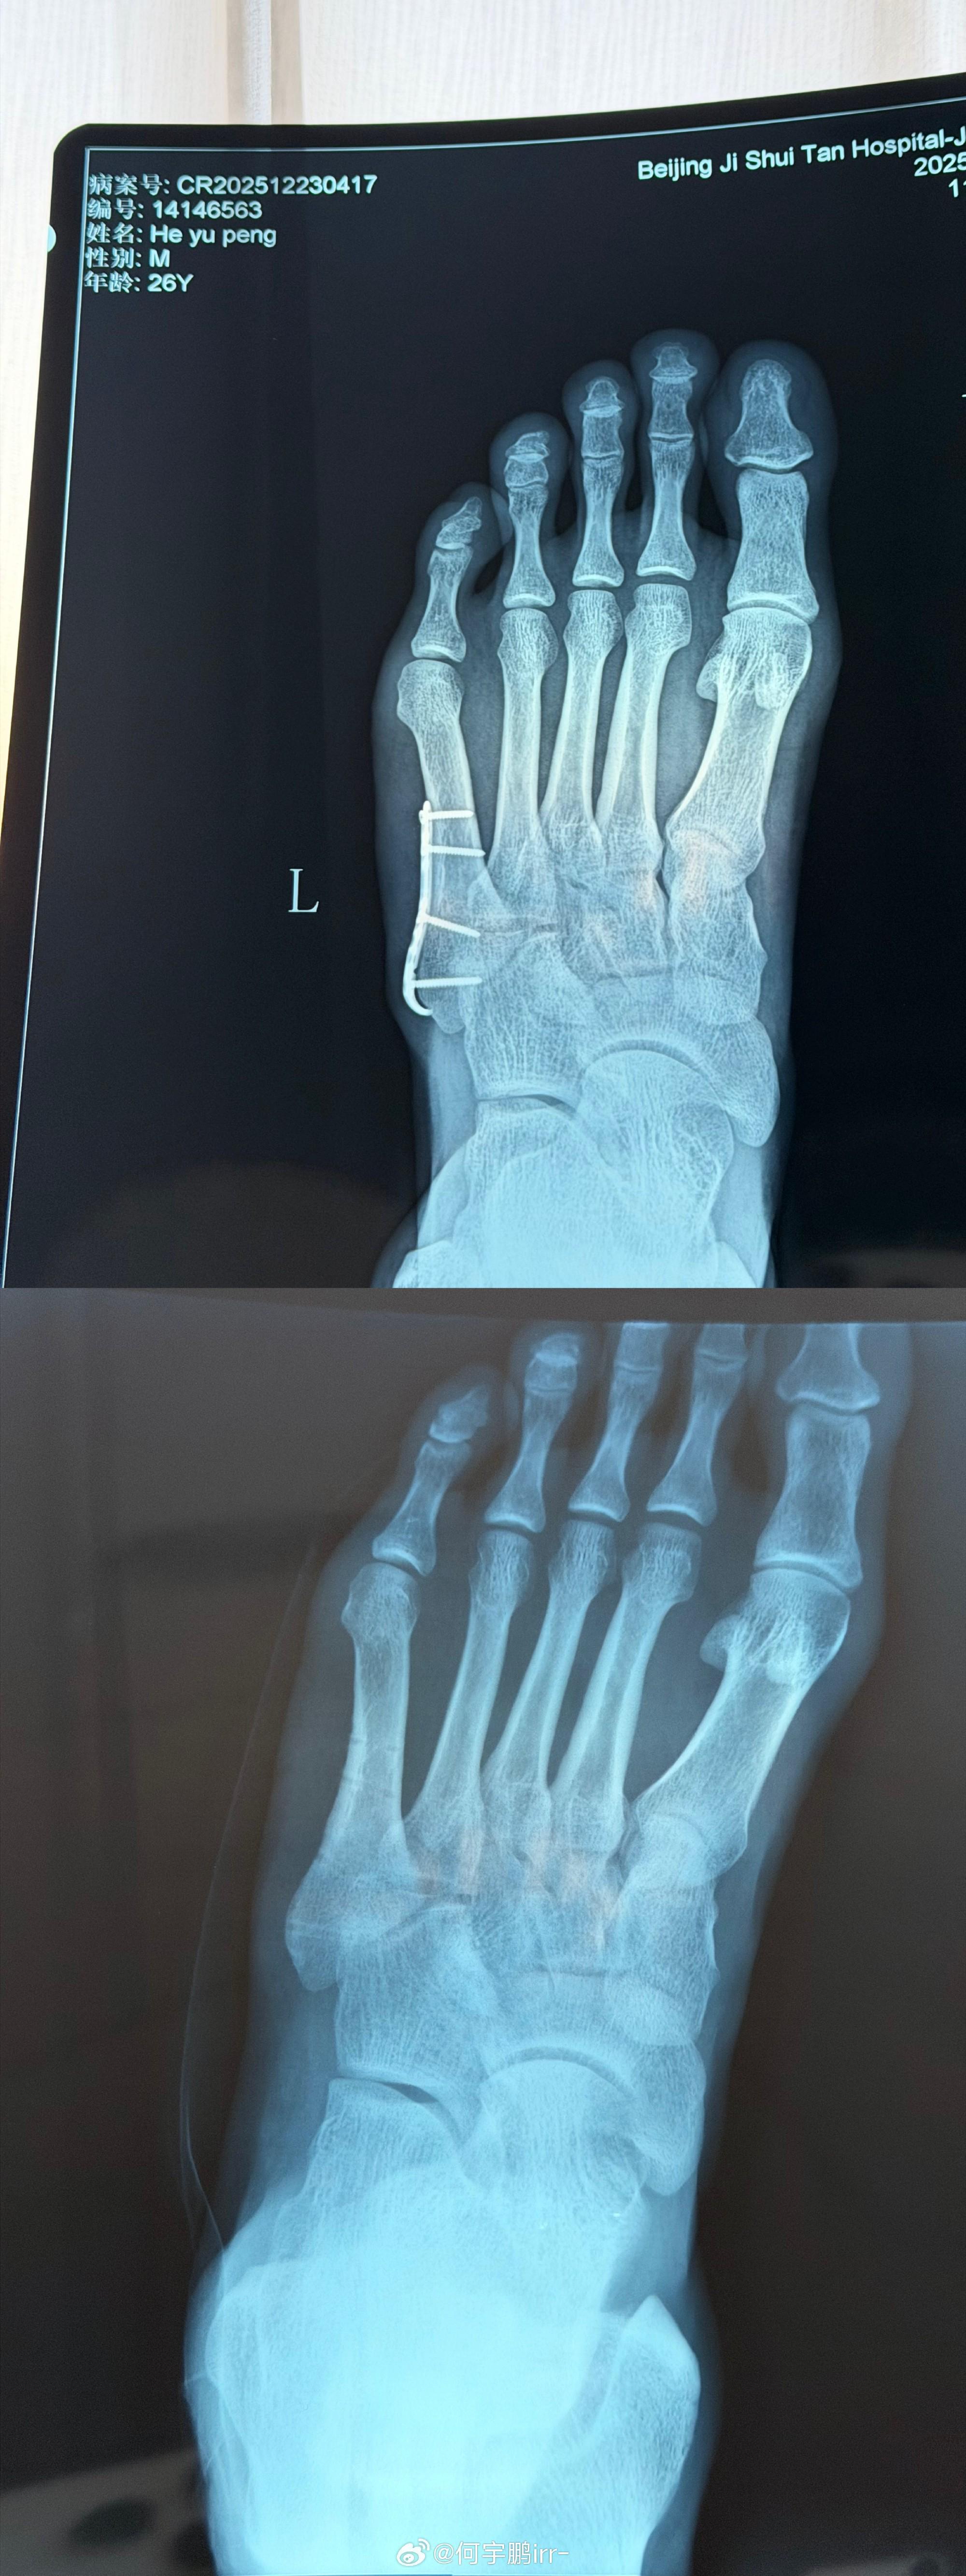

北京時間12月25日,北京國安球員何宇鵬在社交媒體上分享了自己摘除左腳鋼板的照片。

何宇鵬寫道:“終于要和身體里這個‘鐵哥們’說再見了

雖說為了你足球鞋都大了半碼哈哈哈!但也非常感謝8個月的保駕護航,現(xiàn)在,是時候說再見了! 從一開始不敢置信可以帶著鋼板踢球,到二次手術(shù)圓滿結(jié)束,都不得不提我的大功臣,感謝積水潭孫旭主任用超高的醫(yī)術(shù)精密地修補了我的身體! 也感謝葆石頭康復(fù)與 的鼎力支持!愿每一次傷愈都能變得更堅韌!”